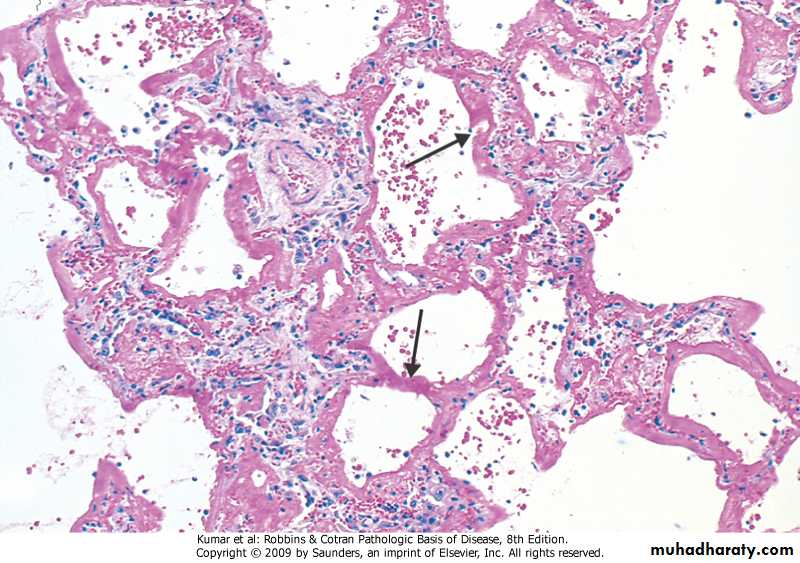

Diffuse alveolar damage, hyaline membrane